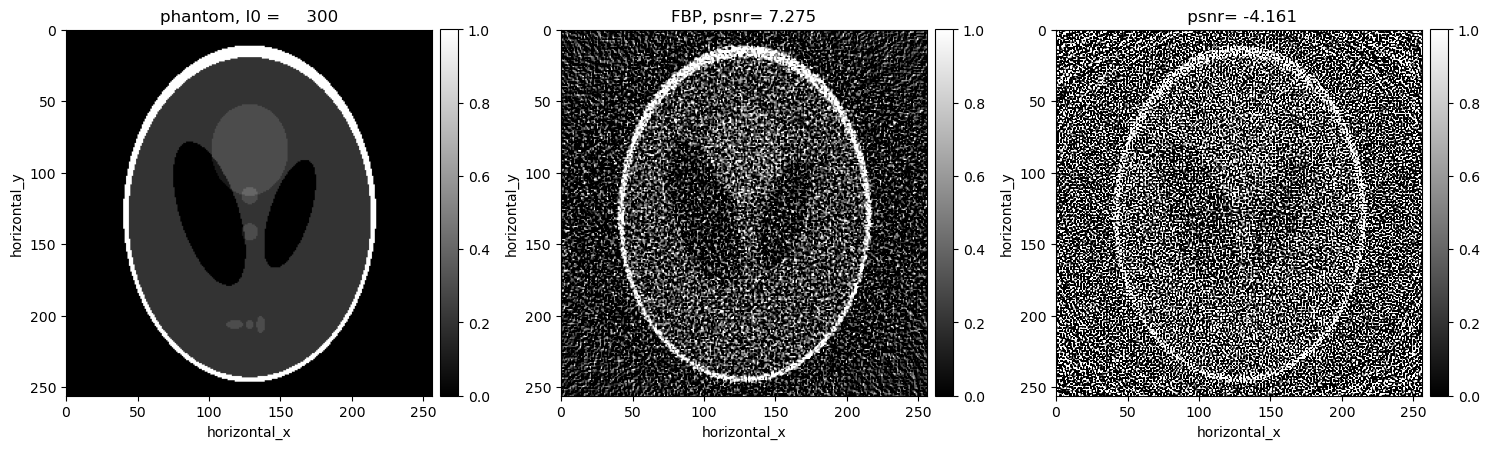

[11]:

show2D([phantom, recon_fbp, recon_ls ], ["phantom, I0 = %7.0f" % (background_counts), "FBP, psnr= %5.3f" % (psnr_fbp),\

" psnr= %5.3f" % (psnr_ls)], \

cmap=cmap, fix_range =(0,1), num_cols=3, size=(15,10), origin='upper-left')

../../_images/demos_LS_WLS_KL_TotalVariation_17_0.png

The KL reconstruction is better than the WLS reconstruction which is better than the LS reconstruction. However, all the above reconstructions are worse than the FDK reconcstruction and seem to be overfitting to the noise. In the next section, we consider reconstructions with TV regularisation.